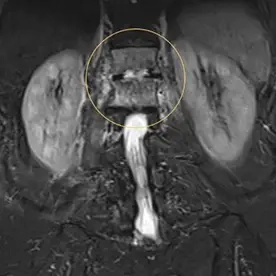

In der angefertigten MRT des LWS und des Abdomens zeigt sich eine kräftige T2w-Signalanhebung in den Wirbelkörpern BWK 12 und LWK 1 mit Irregularitäten der Abschlussplatten (Bild 1). Die angrenzende Psoasmuskulatur zeigt sich auch signalalteriert, betont auf der rechten Seite (Bild 2). Bei der Kontrastmittel-Unterstützer-Untersuchung zeigt sich ein kräftiges Enhancement in den Wirbelkörpern und der angrenzenden Muskulatur (Bild 3). Besonders auf der rechten Seite zeigen sich zudem auch abszessartige Formationen (Bild 4).

Der Befund ist vereinbar mit einer Spondylodiszitis von BWK 12/LWK 1 mit Absenkung in den Musculus psoas beidseits, rechtsbetont, differentialdiagnostisch ist hier an eine Tuberkulose als Ursache zu denken.